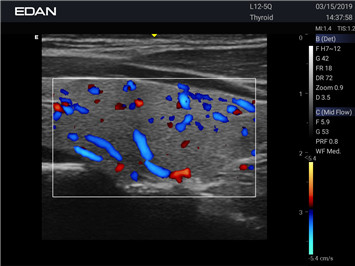

- Machine Type 4D Colour Doppler Ultrasound Machine

- Adaptive Doppler imaging Frequency Compounding Imaging ,- Adaptive Spatial Compounding Imaging ,- Harmonic Imaging ,- Adaptive Speckle Reduction Imaging (eSRI)

- Spectrum Enhancement ,- B mode Auto Optimization ,- Color mode Auto Optimization

- PW mode Auto Optimization